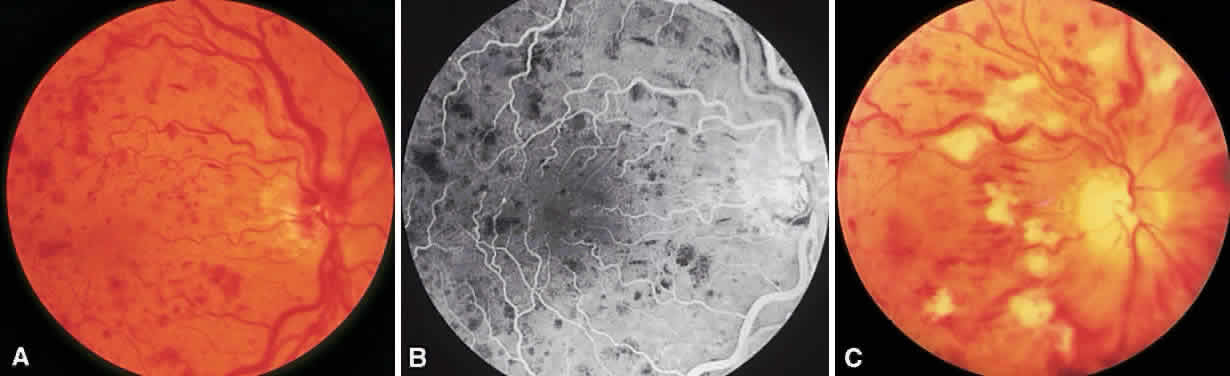

CRVOs are usually described as “ischemic” or “nonischemic” based on clinical examination and FA findings (Fig. 6). Roughly 75% to 80% of CRVOs are nonischemic. However, up to 34% of these will progress to the ischemic type usually within 1 year.46,47,50,51 An eye with a nonischemic CRVO typically has minimal capillary nonperfusion on FA, relatively few intraretinal hemorrhages, and a better visual prognosis than the ischemic variety. Ischemic CRVOs, conversely, have widespread capillary nonperfusion and are associated with a worse visual prognosis with increased risk of rubeosis iridis and neovascular glaucoma.52

Fig. 6. Nonischemic (A and B) and ischemic (C) central retinal vein occlusion.